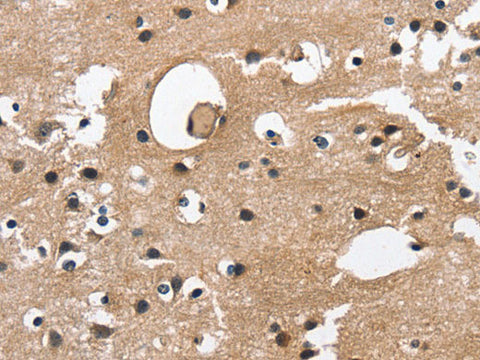

Reactivity Human, Mouse

Applications IHC

Immunogen Recombinant protein of human CAMK1D

Cellular Localization Cytoplasm. Nucleus. Predominantly cytoplasmic (Probable). Also nuclear upon activation.

IHC 1:50-1:200